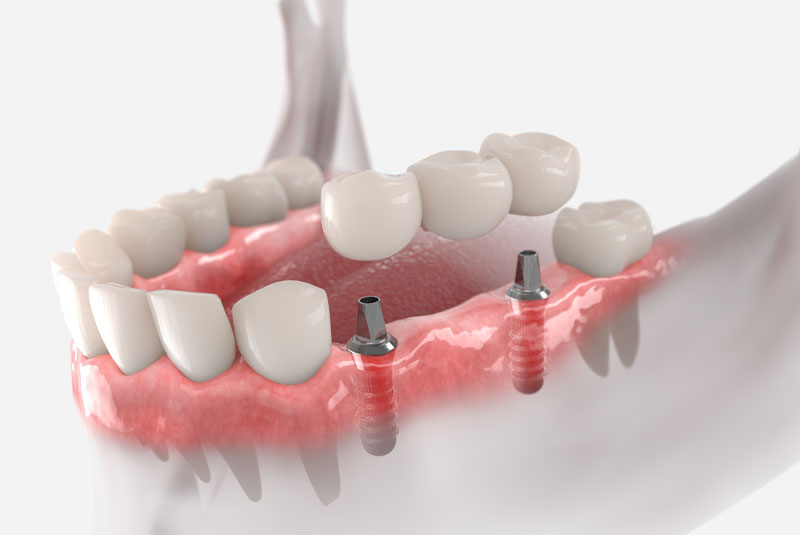

We now offer a Full Warranty on all Full Mouth Implant Treatments with a Permanent Zirconia Bridge! This gives you peace of mind to know that you are not only getting great value when you move forward with the treatment, but that this treatment will stand the test of time!